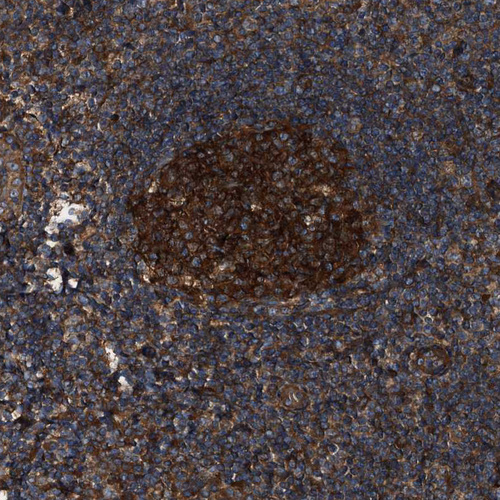

Immunohistochemical staining of human cerebral cortex, colon, lymph node and testis using Anti-PEX5 antibody HPA039259 (A) shows similar protein distribution across tissues to independent antibody HPA039260 (B).